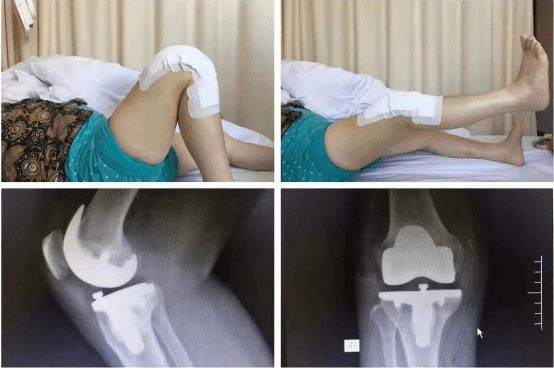

髌骨脱位手术

擅长治疗各种骨关节外伤、骨关节疾病。手术方面擅长髋、膝关节置换术、膝关节单髁置换术、胫骨高位截骨术、股骨颈骨折及转子间骨折等手术。富血小板血浆(PRP)治疗骨关节炎。擅长关节镜下膝关节交叉韧带重建、半月板损伤缝合、髌骨脱位、肩袖修补,肩峰撞击征、钙化性肌腱炎,肱二头肌长头腱炎,髋关节盂唇损伤、髋关节撞击征、踝关节不稳、踝关节韧带损伤、肩关节不稳、肩周炎、各类关节内骨折、关节脱位的手术治疗。